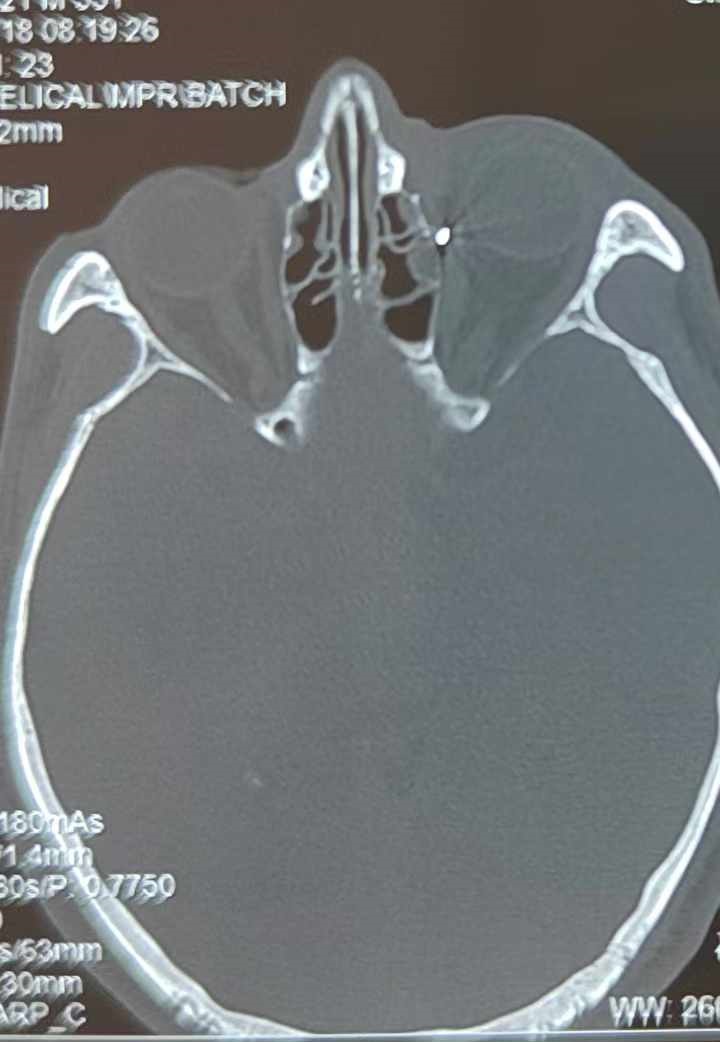

從CT報(bào)告中可以看出,高先生眼內(nèi)的異物不是很大,但位于眼窩深處,緊鄰鼻骨,從CT影像判斷應(yīng)該是金屬或合金異物。一般臨床上遇到這樣的情況,醫(yī)生會(huì)建議“保守觀(guān)察”,若異物傷及神經(jīng)、發(fā)生炎癥感染等,則需到條件較好、有眼眶病和眼外傷專(zhuān)業(yè)醫(yī)師的醫(yī)院進(jìn)行二期眶內(nèi)異物取出術(shù)(2021年《中國(guó)眼眶異物診斷和治療專(zhuān)家共識(shí)》)。

李海波博士介紹,眶內(nèi)異物想要通過(guò)手術(shù)取出,難度很大,一是因?yàn)槲恢秒[匿,無(wú)法實(shí)現(xiàn)可視化操作;二是如果是磁性異物,現(xiàn)有手術(shù)工具磁性強(qiáng)度有限,很難吸出這么深的異物;三是可操作空間極為狹小,眶周軟組織多,異物周邊包裹緊密,像高先生這種情況,異物周邊還有很多神經(jīng)、血管,手術(shù)難度更高。